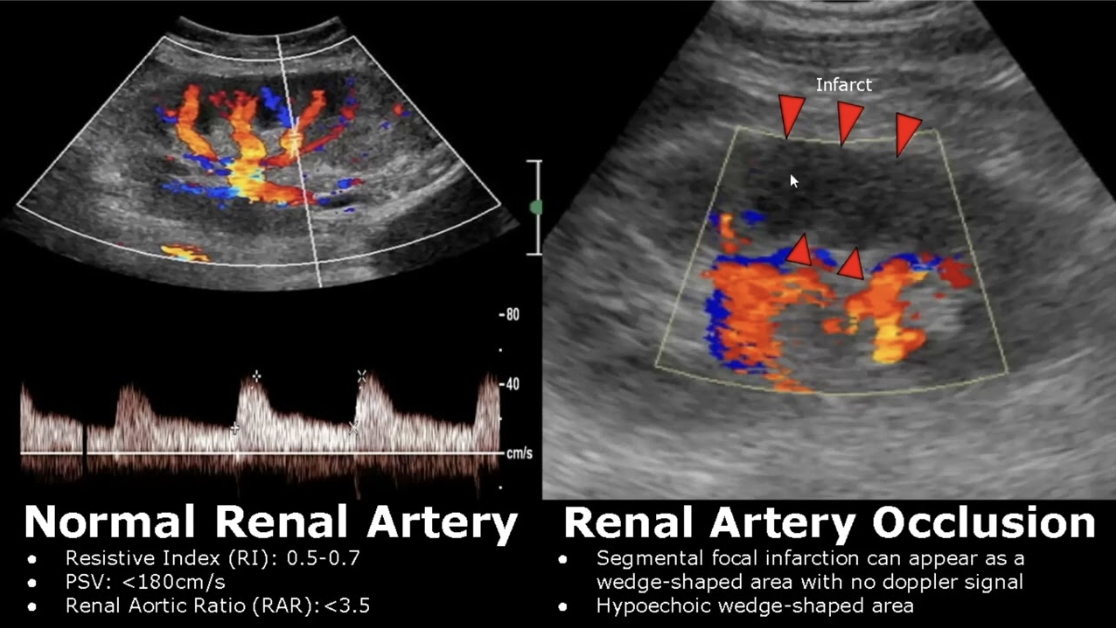

RAS Imaging: Duplex Ultrasonography

Ultrasound image + Doppler

Determine occlusion site + severity